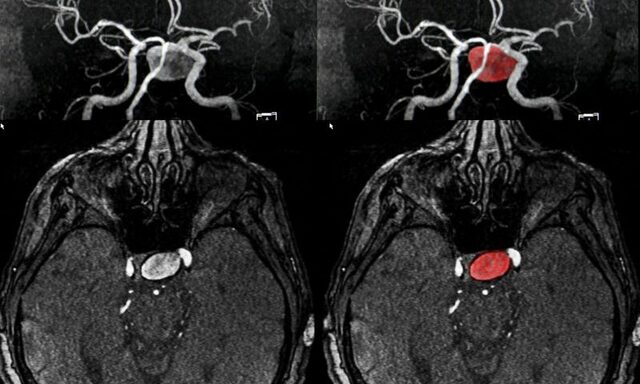

• La arteriografia por Egas Moniz

La arteriografia por Egas Moniz

Descrita por Egas Moniz, usando líquido radiopaco, con el fin de diagnosticar los trastornos cerebrales, gana en 1949 el Premio Nobel por su aporte a las ciencias de la salud.

• Aneurisma Silviano

Aneurisma Silviano

El doctor Dandy diagnostica un aneurisma silviano y para tratarlo ocluye la carótida en el cuello

• Los clips

Los clips

El cirujano Dandy inicia el empleo de los clips para aneurismas, que mas adelantes seran modificados y mejor realizados por el neurocirujano YASARLGIL